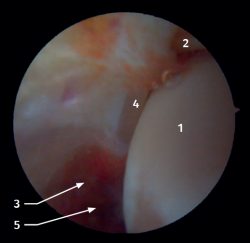

Visión artroscópica anterior

El 20% del LTPA es intraarticular(7). Cuando realizamos un acceso anteromedial del tobillo dirigiendo el artroscopio hacia lateral podemos ver las fibras distales del LTPA con su disposición oblicua y su continuación con el ligamento peroneo-astragalino anterior (Figura 2). Si avanzamos dentro de la articulación tibioastragalina, veremos la articulación tibioperonea distal con el receso sindesmal ocupado de tejido sinovial (Figura 3).

Figura 2. Visión artroscópica anterolateral del tobillo derecho. 1: cúpula astragalina; 2: cara anterior de la tibia; 3: peroné; 4: fibras distales del ligamento tibioperoneo anterior; 5: ligamento peroneo-astragalino anterior.